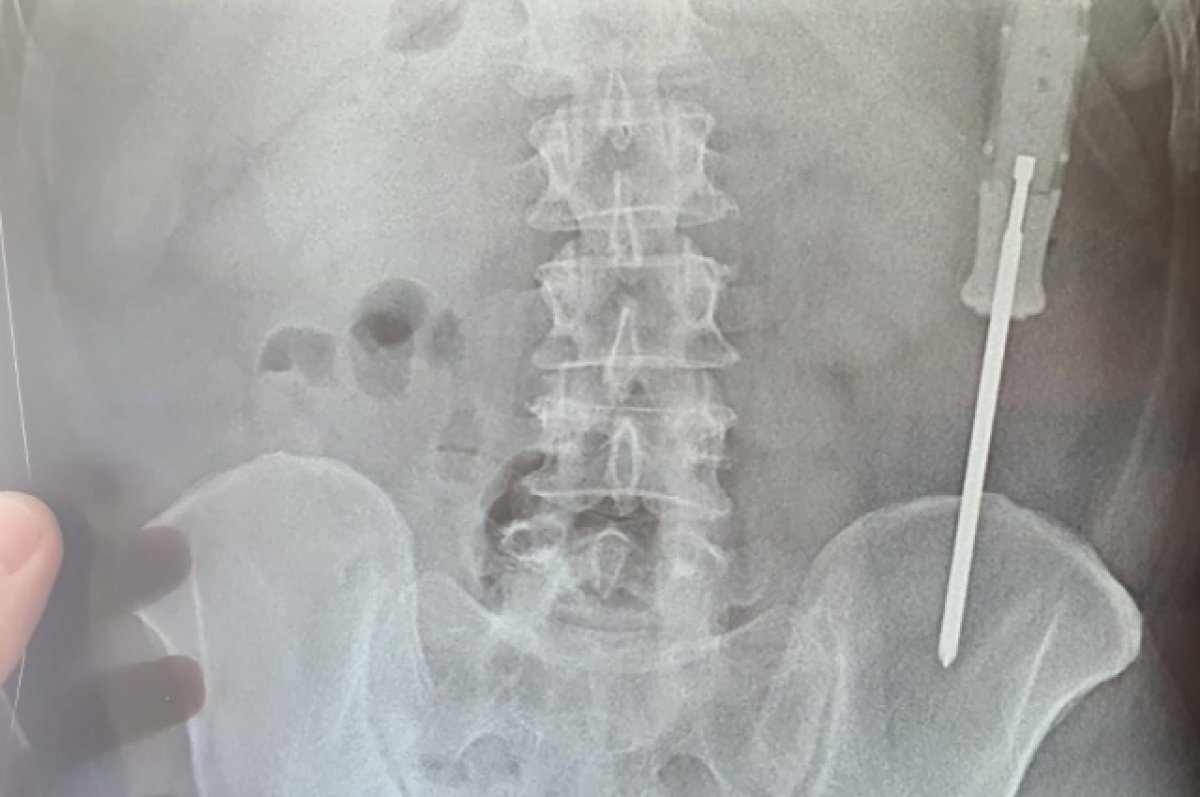

Из одного пациента извлекли отвертку.

«Бывают такие травмирующие ситуации, когда предмет достать крайне сложно, например, свечка сильно крошится. А один из пациентов засунул отвертку внутрь себя ручкой вверх, очень долго ходил с ней и в итоге началось воспаление, случился жесточайший перитонит, мужчина полтора месяца лежал в больнице. Он вернулся домой глубоким инвалидом», – отметил Дмитрий Игоревич.